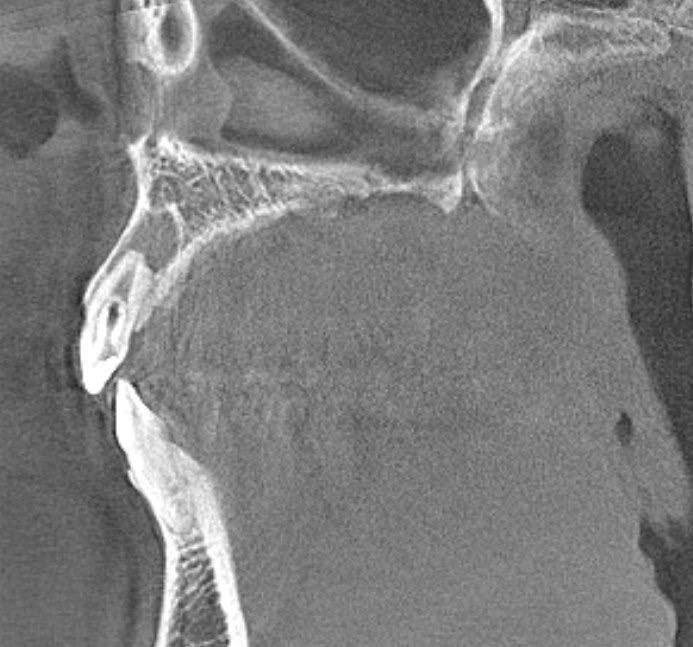

🦷 Π›Π•Π§Π•ΠΠ˜Π• DENS IN CERVICIS (DENS INVAGINATUS) Как Π²Ρ‹ ΠΏΠΎΠΌΠ½ΠΈΡ‚Π΅, Ρ€Π°Π½Π΅Π΅ я ΡƒΠΆΠ΅ рассказывала ΠΎ Ρ‚Π°ΠΊΠΎΠΌ интСрСсном Π΄ΠΈΠ°Π³Π½ΠΎΠ·Π΅, ΠΊΠ°ΠΊ dens invaginatus ΠΈΠ»ΠΈ Β«Π±Π΅Ρ€Π΅ΠΌΠ΅Π½Π½Ρ‹ΠΉ Π·ΡƒΠ±Β». БСгодня Ρ…ΠΎΡ‡Ρƒ ΠΏΠΎΠ΄Π΅Π»ΠΈΡ‚ΡŒΡΡ клиничСским случаСм лСчСния 2.2 Π·ΡƒΠ±Π° с Π΄Π°Π½Π½ΠΎΠΉ Π°Π½ΠΎΠΌΠ°Π»ΠΈΠ΅ΠΉ развития. πŸ”Ή Π”ΠΈΠ°Π³Π½ΠΎΠ·: Dens invaginatus (Ρ‚ΠΈΠΏ I ΠΏΠΎ классификации Oehlers) πŸ”Ή Π’Π°ΠΊΡ‚ΠΈΠΊΠ°: ΠšΠΎΠ½ΡΠ΅Ρ€Π²Π°Ρ‚ΠΈΠ²Π½ΠΎΠ΅ Π»Π΅Ρ‡Π΅Π½ΠΈΠ΅ ΠΏΠΎ стандарту β€” Π² Π΄Π²Π° посСщСния. ΠŸΠ΅Ρ€Π²ΠΎΠ΅ посСщСниС: - Π€ΠΎΡ€ΠΌΠΈΡ€ΠΎΠ²Π°Π½ΠΈΠ΅ доступа ΠΊ ΠΊΠΎΡ€Π½Π΅Π²Ρ‹ΠΌ ΠΊΠ°Π½Π°Π»Π°ΠΌ - ΠœΠ΅Ρ…Π°Π½ΠΈΡ‡Π΅ΡΠΊΠ°Ρ ΠΈ мСдикамСнтозная ΠΎΠ±Ρ€Π°Π±ΠΎΡ‚ΠΊΠ° ΠΊΠ°Π½Π°Π»ΠΎΠ² - Π’Ρ€Π΅ΠΌΠ΅Π½Π½ΠΎΠ΅ ΠΏΠ»ΠΎΠΌΠ±ΠΈΡ€ΠΎΠ²Π°Π½ΠΈΠ΅ Π³ΠΈΠ΄Ρ€ΠΎΠΎΠΊΠΈΡΡŒΡŽ ΠΊΠ°Π»ΡŒΡ†ΠΈΡ Π’Ρ‚ΠΎΡ€ΠΎΠ΅ посСщСниС: - Π£Π΄Π°Π»Π΅Π½ΠΈΠ΅ Π²Ρ€Π΅ΠΌΠ΅Π½Π½ΠΎΠΉ пасты - ΠžΠΊΠΎΠ½Ρ‡Π°Ρ‚Π΅Π»ΡŒΠ½ΠΎΠ΅ ΠΏΠ»ΠΎΠΌΠ±ΠΈΡ€ΠΎΠ²Π°Π½ΠΈΠ΅ ΠΊΠΎΡ€Π½Π΅Π²ΠΎΠ³ΠΎ ΠΊΠ°Π½Π°Π»Π° биокСрамичСским силСром - ВосстановлСниС ΠΊΠΎΡ€ΠΎΠ½ΠΊΠΎΠ²ΠΎΠΉ части Π·ΡƒΠ±Π° свСтоотвСрТдаСмым ΠΊΠΎΠΌΠΏΠΎΠ·ΠΈΡ‚ΠΎΠΌ с ΠΏΡ€ΠΈΠΌΠ΅Π½Π΅Π½ΠΈΠ΅ΠΌ Ρ‚Π΅Ρ…Π½ΠΎΠ»ΠΎΠ³ΠΈΠΈ армирования Ribbond 🎯 Π’Π°ΠΊΡ‚ΠΈΠΊΠ° Π²Ρ‹Π±Ρ€Π°Π½Π° с ΡƒΡ‡Π΅Ρ‚ΠΎΠΌ анатомичСских особСнностСй Π·ΡƒΠ±Π° ΠΈ ΠΏΡ€ΠΎΡ„ΠΈΠ»Π°ΠΊΡ‚ΠΈΠΊΠΈ Π²ΠΎΠ·ΠΌΠΎΠΆΠ½Ρ‹Ρ… ослоТнСний. ΠžΡ‡Π΅Π½ΡŒ Π²Π°ΠΆΠ½ΠΎ Π½Π° этапС диагностики ΠΏΡ€Π°Π²ΠΈΠ»ΡŒΠ½ΠΎ ΠΎΡ†Π΅Π½ΠΈΡ‚ΡŒ Π³Π»ΡƒΠ±ΠΈΠ½Ρƒ ΠΈΠ½Π²Π°Π³ΠΈΠ½Π°Ρ†ΠΈΠΈ ΠΈ риск ΠΏΠ΅Ρ€Ρ„ΠΎΡ€Π°Ρ†ΠΈΠΈ! πŸ“£ КоллСги, Π΄Π΅Π»ΠΈΡ‚Π΅ΡΡŒ Π² коммСнтариях: Ρƒ ΠΊ

Как Π²Ρ‹ ΠΏΠΎΠΌΠ½ΠΈΡ‚Π΅, Ρ€Π°Π½Π΅Π΅ я ΡƒΠΆΠ΅ рассказывала ΠΎ Ρ‚Π°ΠΊΠΎΠΌ интСрСсном Π΄ΠΈΠ°Π³Π½ΠΎΠ·Π΅, ΠΊΠ°ΠΊ dens invaginatus ΠΈΠ»ΠΈ Β«Π±Π΅Ρ€Π΅ΠΌΠ΅Π½Π½Ρ‹ΠΉ Π·ΡƒΠ±Β».

БСгодня Ρ…ΠΎΡ‡Ρƒ ΠΏΠΎΠ΄Π΅Π»ΠΈΡ‚ΡŒΡΡ клиничСским случаСм лСчСния 2.2 Π·ΡƒΠ±Π° с Π΄Π°Π½Π½ΠΎΠΉ Π°Π½ΠΎΠΌΠ°Π»ΠΈΠ΅ΠΉ развития.

πŸ”Ή Π”ΠΈΠ°Π³Π½ΠΎΠ·: Dens invaginatus (Ρ‚ΠΈΠΏ I ΠΏΠΎ классификации Oehlers)

🎯 Π’Π°ΠΊΡ‚ΠΈΠΊΠ° Π²Ρ‹Π±Ρ€Π°Π½Π° с ΡƒΡ‡Π΅Ρ‚ΠΎΠΌ анатомичСских особСнностСй Π·ΡƒΠ±Π° ΠΈ ΠΏΡ€ΠΎΡ„ΠΈΠ»Π°ΠΊΡ‚ΠΈΠΊΠΈ Π²ΠΎΠ·ΠΌΠΎΠΆΠ½Ρ‹Ρ… ослоТнСний. ΠžΡ‡Π΅Π½ΡŒ Π²Π°ΠΆΠ½ΠΎ Π½Π° этапС диагностики ΠΏΡ€Π°Π²ΠΈΠ»ΡŒΠ½ΠΎ ΠΎΡ†Π΅Π½ΠΈΡ‚ΡŒ Π³Π»ΡƒΠ±ΠΈΠ½Ρƒ ΠΈΠ½Π²Π°Π³ΠΈΠ½Π°Ρ†ΠΈΠΈ ΠΈ риск ΠΏΠ΅Ρ€Ρ„ΠΎΡ€Π°Ρ†ΠΈΠΈ!